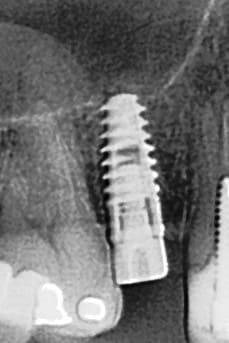

tiens...un ptit cas...

dans ce petit cas...j'ai commencé avec le kit MIS...et fini ma voie crestale avec le kit HBS...

ok, c'est un mini soulevé...mais bon , c'est un exemple...

juste une précision...premier foret 1.3mm sur 8mm...expansion pour mettre un implant de 4x10...

j'ai juste "léché" la préparation du site final avec le foret terminal du système...sur 8mm...avant d'insérer l'implant...stab primaire au top...blocage à 40 Ncm...

rien...une cloison du sinus...;-))

???? tu as un pano ou un scan je ne situe pas ça comme une cloison, mais je vois mal.

j'ai la pano au cab...pas de problème...çà peut aussi être un épaississement de la membrane dans ce cloisonnement...il a eu un bon rhume quelques semaines avant...